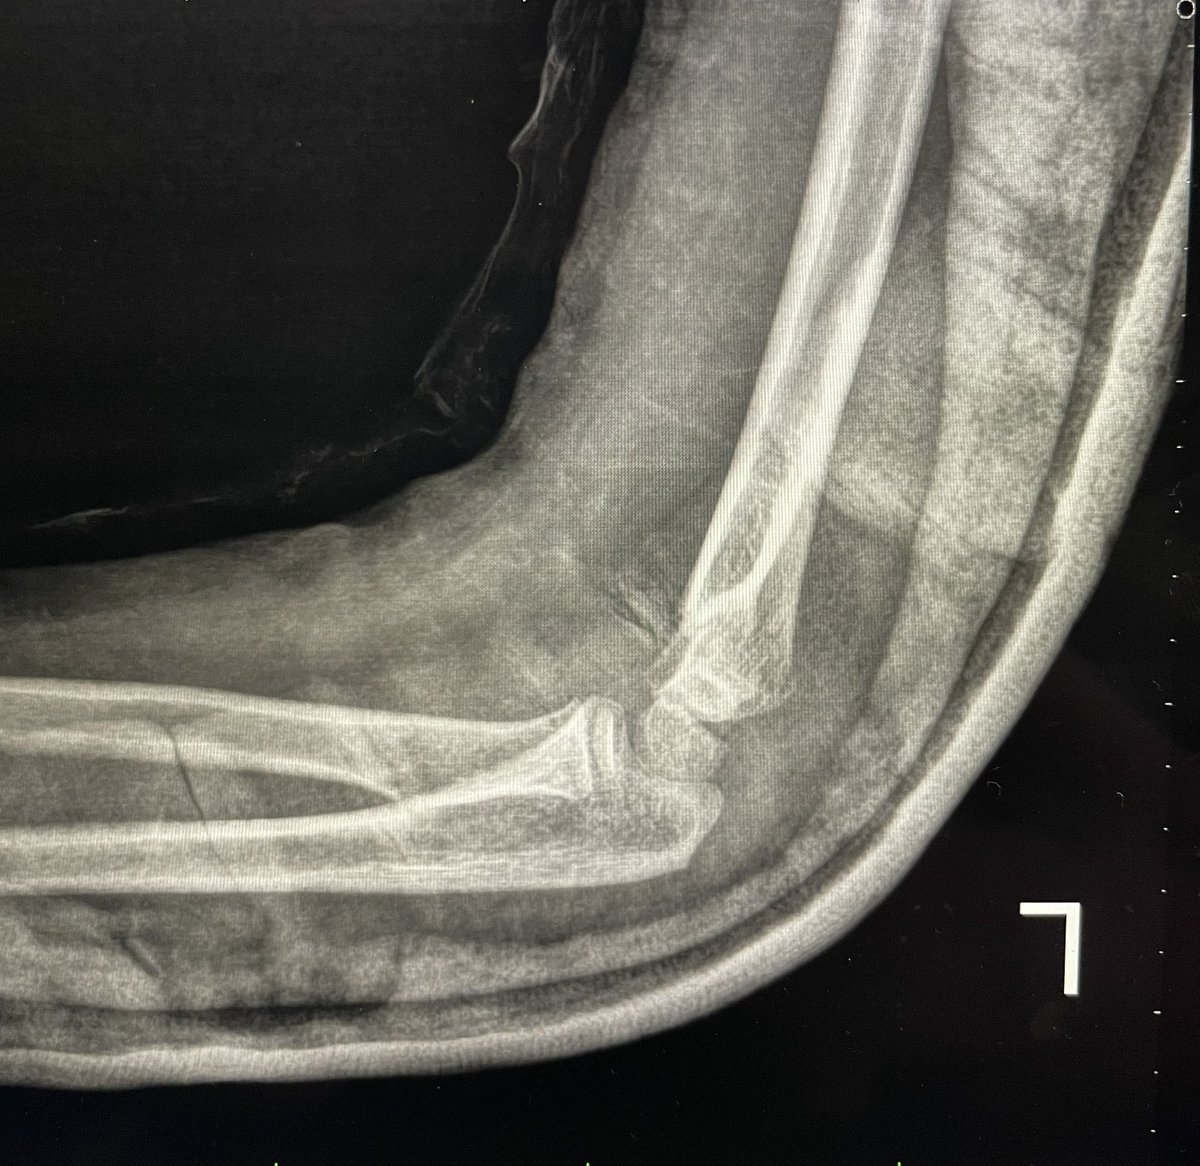

58 male fall from height last week !

Hx: HTN , CAD

Medicine :Aspirin 81 , Clopidogrel

When I aspirate hematoma there was about 6 ml blood

this is the pre_after reduction and the follow up today

He is not elderly in shape and body he looks like 40 !

1/2

@#orthotwitter